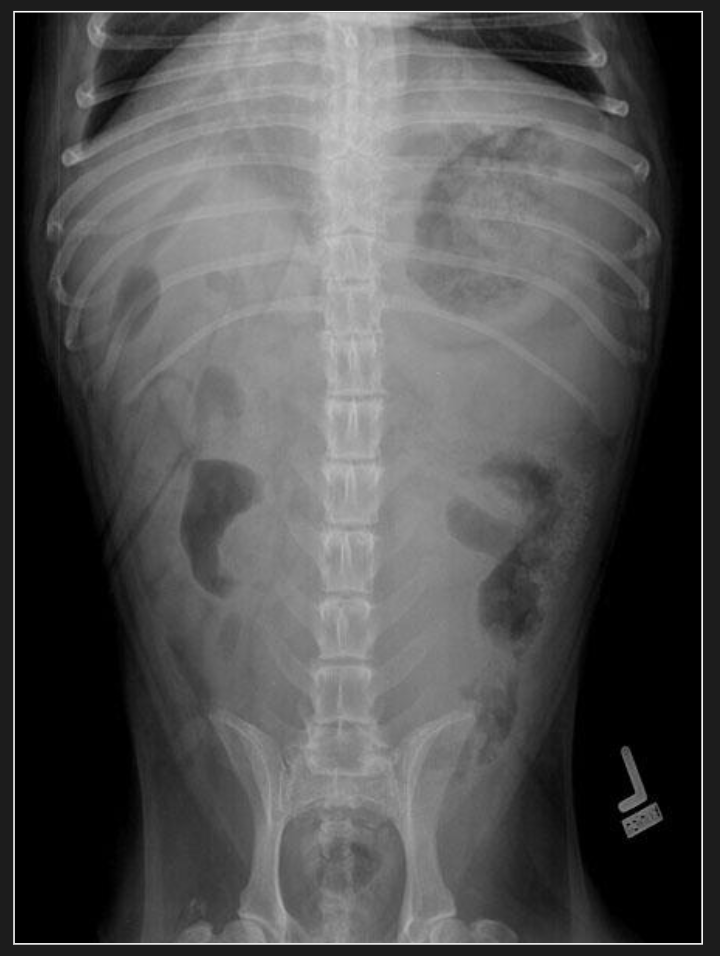

Vue ventro-dorsale

Positionnement :

- L’animal est en décubitus dorsal et peut être dans un coussin en V.

- Maintenir les membres pelviens en position anatomique normale, légèrement en extension caudalement.

- Bien centrer et aligner le sternum et la ligne blanche.

- Placer le bassin bien à plat et symétrique dans le coussin en V.

Collimation :

- Crânialement, la collimation doit inclure l’apophyse xiphoïde, afin de bien inclure l’entièreté du foie et de l’estomac.

- Caudalement, elle doit aller jusqu’aux hanches.

- Latéralement, s’assurer de bien inclure les parois de l’abdomen.

- Si l’animal est trop grand pour inclure la collimation suggérée dans un seul cliché, prendre deux radiographies afin d’inclure toute la région à radiographier.

Centrage :

- Centrer le faisceau tout juste crânialement à l’ombilic.

Orientation :

- S’assurer que la partie crâniale de l’animal est vers le haut et la partie caudale est vers le bas de l’écran.

- S’assurer que l’image est bien inversée, c’est-à-dire que la gauche de l’animal est à droite, et que la droite de l’animal est à gauche de l’écran.

Mesure :

- Une fois l’animal en position radiographique, placer la règle au point le plus haut (généralement à la dernière côte) afin de prendre une mesure.